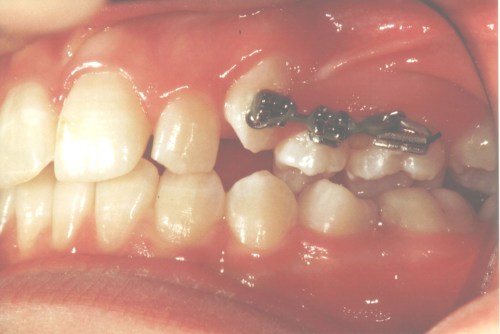

En fast bøjle består af små brackets, som limes fast på tænderne. Tværs over tænder og brackets sættes en bue i metaltråd ("togskinner"). Den faste bøjle kan kun sættes på og fjernes på tandklinikken.

Billederne nedenfor viser en fast bøjle og en sektionsbue, som er en fast bøjle over nogle få tænder.